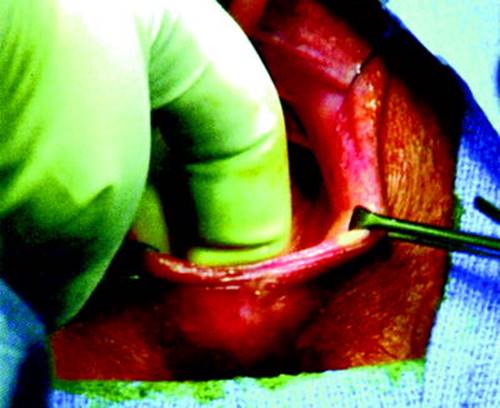

Fig. 18.4

The skin of the labia minor has been previously sewn across the midline, most likely at the time of the repair of a midline episiotomy